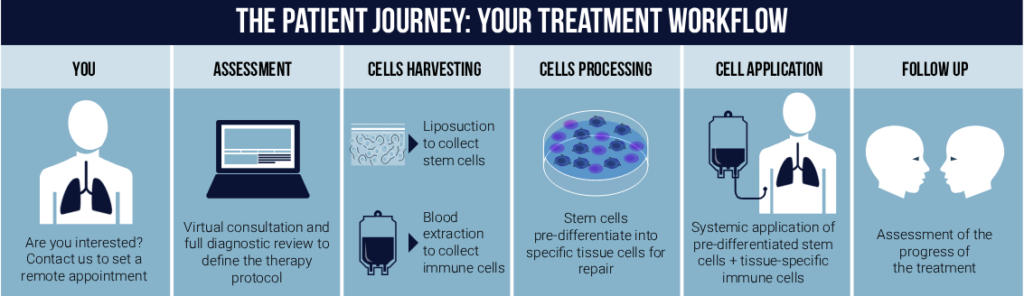

Moviglia Method therapy is a simple and effective procedure completed in a single outpatient visit. Here’s a step-by-step guide to what patients can expect:

EVALUATION PRE-TREATMENT

Clinical evaluation is complemented with Pulmonary function tests (Spirometry, lung diffusion, oximetry) and imaging (Chest X ray and CT scan).

HARVESTING

Two types of cells are needed for the treatment: stem cells and tissue-specific effector lymphocytes. The stem cells are extracted from subcutaneous fat, which is done by performing a micro liposuction procedure that only needs local anesthesia. Immune cells are obtained from the patient’s peripheral blood.

CELL PROCESSING

The collected fat is processed to isolate and expand the stem cells. The combination of the stem cells and the tissue specific effector lymphocytes facilitates the pre differentiation of the stem cells into the specific cells that the tissue needs to repair the damage (lung and vascular structures).

CELL APPLICATION

Pre-differentiated cells, together with tissue-specific lymphocytes, are given by intravenous infusion. The infusion is repeated every 4 to 8 weeks for one year. Lung function tests are performed every 6 months.